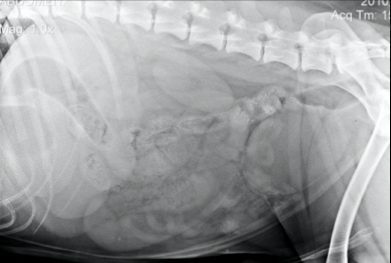

Anamnèse : Elkhound norvégien, femelle, 16 ans, présentée pour faiblesse et ataxie des membres pelviens.

Qu’en pensez-vous?

Spondylose, mais n’explique pas les signes cliniques